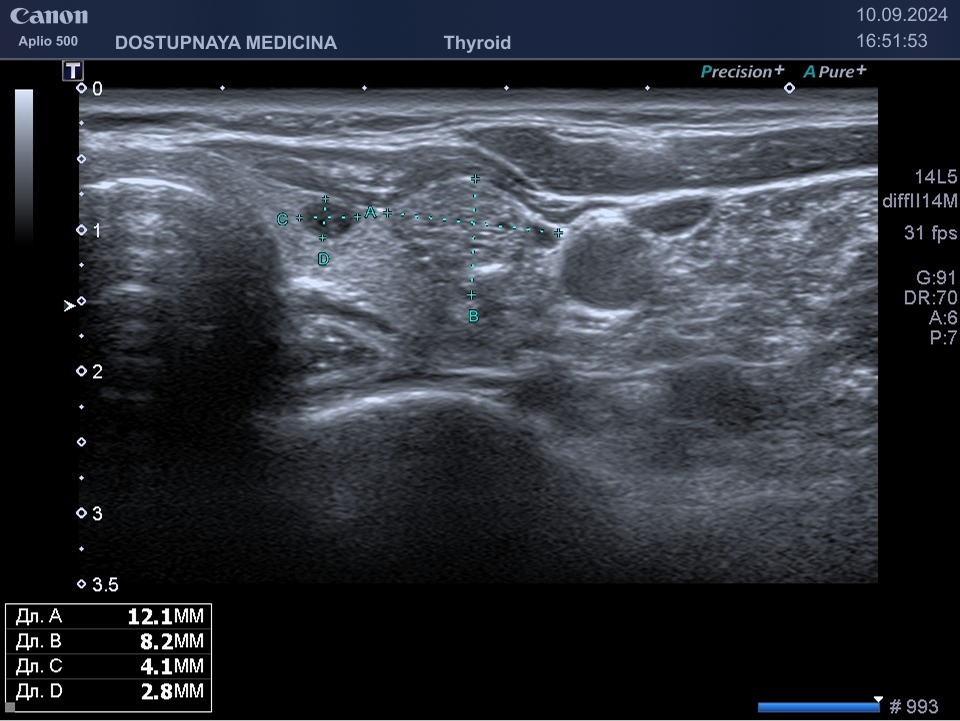

В ультразвуковой диагностике существует классификация образований щитовидной желзы по TIRADS, которая по различным критериям определяет степень онкоопастности того или ионого узла. При оценке учитывается эхоструткура образования ( кистозная, губчатая, солидная или солидно-кистозная), эхогенность ( анэхогенное, гиперэхогенное, гипоэхогенное), пространственная ориентация горизонтальная, вертикальная, неопределённая), контуры образования (ровные, дольчатые, зазубренные с острыми углами), наличие эхогенных включений( макрокальцинаты, микрокальцинаты, периферическая кольцевидная кальцификация). В зависимости от этих критериев выделяют различные категориии объёмных образований в щитовидной железе:

TIRADS 3 – низко подозрительное образование, требующие динамическое наблюдение и тонкоигольной биопсии при размерах узла больше 2.5 см.

TIRADS 4 – умеренно подозрительное образование, требующие динамическое наблюдение и тонкоигольной биопсии при размерах узла больше 1.5 см.

TIRADS 5 – высоко подозрительное образование, требующие динамическое наблюдение и тонкоигольной биопсии при размерах узла больше 1 см.

Большинство узловых образований в щитовидной железе не нуждаются в лечении и требуют лишь наблюдения путём повторного ультразвуковых исследований.

При подозрении на озлокачествление и увеличении узла в размерах требуется тонкоигольная пункционная биопсия с полседующим цитологическим исследованием, полученного материала.